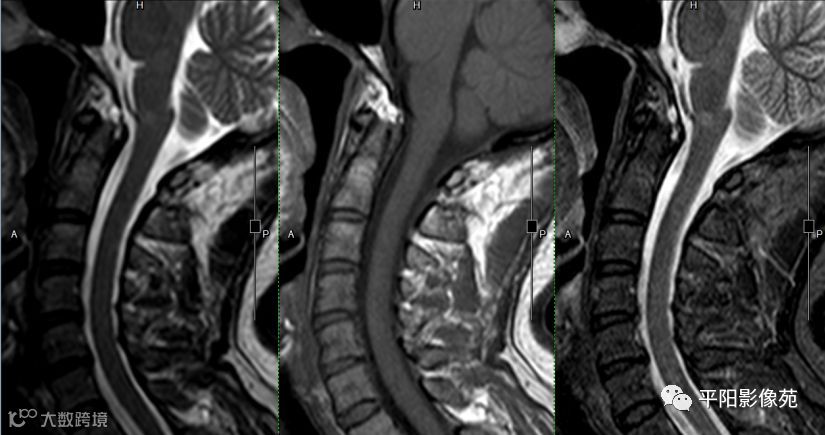

影像表现

延髓与颈脊髓交界区见斑片状长T1长T2信号,抑制序列为高信号,增强后病灶中等强化。

MR是目前唯一能直接显示脊髓炎的影像检查手段。

为长T1长T2信号,边界不清,局部脊髓肿胀膨大,肿胀较轻。矢状位T2加权图可清楚显示病变的范围。

增强:轻度强化或无明显强化。